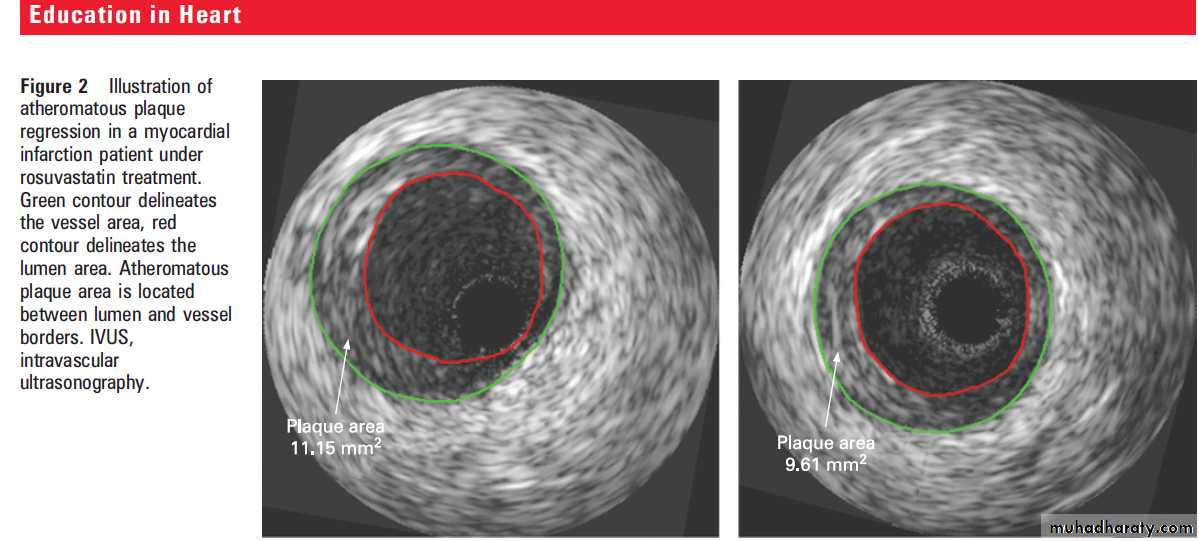

Is plaque regression also possible?

On average, statin treatment diminishes the progressionof coronary atherosclerosis, but regression has sometimes been observed on an individual basis

with serial coronary angiographies. In 2004, using

intravascular ultrasonography (IVUS) analyses (as

illustrated in fig 2), Nissen et al published the results

from the Reversal of Atherosclerosis with Aggressive

Lipid Lowering (REVERSAL) study.

This was arandomised trial in which 502 patients received either 40 mg of pravastatin or an intensive lipid lowering regimen of 80 mg of atorvastatin.

Coronary arteries were assessed by serial IVUS at

baseline and after 18 months of treatment. Initial

LDL-C concentrations (3.9 mmol/l or 150 mg/dl in

both groups) were reduced during the treatment by

27% in the moderate regimen group (pravastatin)

and by 47% in the intensive regimen group.

Two years later, Nissen et al published the

results of a prospective trial, A Study to Evaluatethe Effect of Rosuvastatin on Intravascular

Ultrasound-Derived Coronary Atheroma Burden

(ASTEROID), where 349 patients received 40 mg

of rosuvastatin daily and were evaluated by IVUS

at baseline and after 24 months.

The mean baseline LDL-C of 3.4 mmol/l (130 mg/dl) decreased by 53% while the mean HDL-C value increased by 15% from 1.1 mmol/l (43 mg/dl) at baseline. The

mean change of PAV compared with baseline was

1% for the entire vessel. The total atheroma

volume showed a 6.8% median reduction and the

mean change in atheroma volume in the most

diseased 10 mm subsegment was -6.1 mm3.

Although these two studies do not report impressive values per se with regard to regression of atheroma, one has to keep in mind that they represent valuable evidence that progression may be stopped or even regression of atherosclerotic disease may be achieved, at least in some patients, with the current drugs in high dosages.

Newly developed techniques such as intravascular

ultrasonography have revealed that newly developed statins are able to control and sometimes even to reverse coronary atherosclerotic plaques.In conclusion, because they are efficient, generally